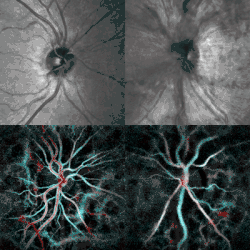

| Fundal photograph showing severe papilledema in the left eye | |

Papilledema or papilloedema is optic disc swelling that is caused by increased intracranial pressure due to any cause.[1] The swelling is usually bilateral and can occur over a period of hours to weeks.[2] Unilateral presentation is extremely rare.

The signs of papilledema that may be seen using an ophthalmoscope include:

- venous engorgement (usually the first signs)

- loss of venous pulsation

- hemorrhages over and/or adjacent to the optic disc

- blurring of optic margins

- elevation of the optic disc

- Paton's lines (radial retinal lines cascading from the optic disc)

Checking the eyes for signs of papilledema should be carried out whenever there is a clinical suspicion of raised intracranial pressure, and is recommended in newly onset headaches. This may be done by ophthalmoscopy or fundus photography, and possibly slit lamp examination.